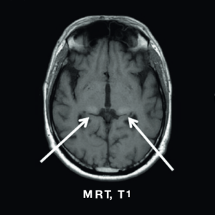

Typische MRT-Befunde sind White Matter Lesions, Schädigungen der weißen Hirnsubstanz und Pulvinar-Zeichen, die sich als Hyperintensität unter T1-Wichtung darstellen. Fabry-Patienten leben oft dauerhaft mit Schmerzen unterschiedlicher Qualität, Intensität und Lokalisierung, dies kann durch standardisierte Fragebögen, z. B. den SF-36, dokumentiert werden.

MRT, T1

mrt_01

Bilaterale Signalerhöhung im posterioren Thalamus (“Pulvinar-Zeichen”)

Mit freundlicher Genehmigung von Prof. Dr. Arndt Rolfs, Universität Rostock